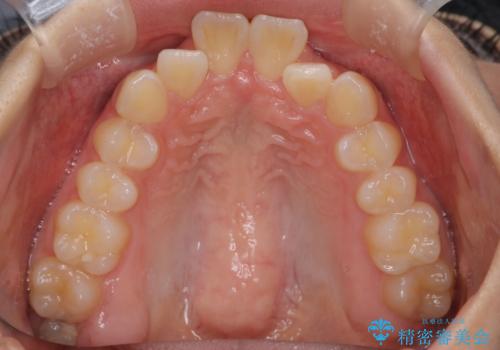

- 前歯が出ていることを主訴に来院されました。

下顎前歯が1本欠損していることもあり、前突はある程度残ることを説明し、インビザラインにて治療を行いました。

今回は抜歯矯正ではなく歯列弓の拡大とIPR、遠心移動を行って配列することができました。